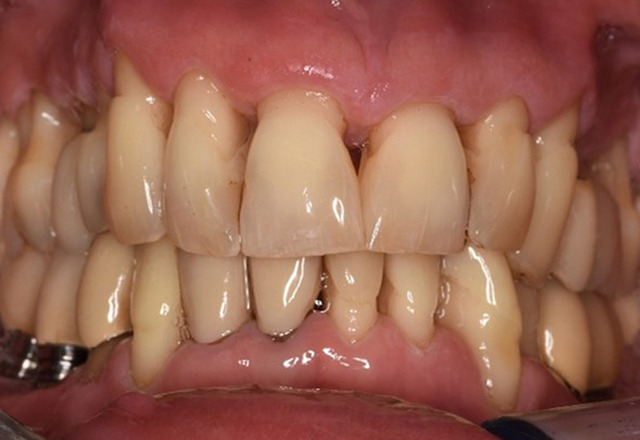

The healthy patient with pre-existing periodontal disease & peri-implantitis

The 68-year-old patient has no general health conditions and is not taking any medication that may be relevant to her oral health, and her lifestyle does not pose any particular risk. The patient has two dental implants (3rd quadrant, for five years) and a previous case of periodontal disease (stage IV, grade B periodontitis) with tooth loss. Currently the periodontal conditions are stable. However, periodontitis significantly increases the biological complications of implantations and there is a risk of implant loss (21). Four recommendations can be determined for the prophylaxis session. more